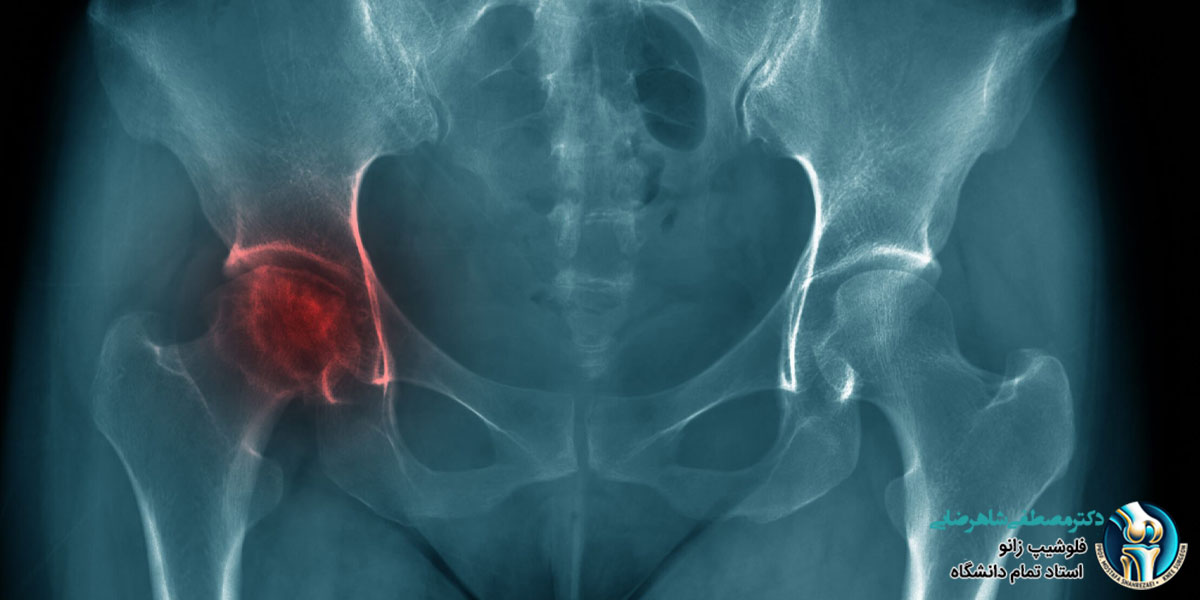

جراحی تعویض مفصل لگن می تواند به افرادی که دچار درد شدید و مشکلات حرکتی در این ناحیه هستند، کمک کند تا راحت تر و بدون درد حرکت کنند . بعد از جراحی، بدن نیاز به زمان دارد تا به مفصل جدید عادت کند. مدت زمان بهبودی برای هر فرد متفاوت است و به عواملی مثل سن، وضعیت سلامتی، مراقبت های بعد از جراحی و انجام تمرینات فیزیوتراپی بستگی دارد. بعضی از افراد بعد از چند هفته می توانند کارهای روزمره خود را انجام دهند، اما برای بعضی دیگر ممکن است ماه ها طول بکشد تا بتوانند دوباره به فعالیت های عادی برگردند.

اگر دچار آرتروز مفصل لگن هستید و نیاز به جراحی تعویض مفصل لگن دارید، یکی از مهم ترین مسائلی که باید در نظر بگیرید مدت زمان بهبودی پس از جراحی است. دکتر مصطفی شاهرضایی، جراح زانو و استاد دانشگاه با توجه به تجربه و تخصص خود در زمینه جراحی های مفصل لگن، می توانند به طور دقیق به شما توضیح دهند که پس از جراحی تعویض مفصل لگن، چه مدت زمانی برای بهبودی نیاز است و چه عواملی بر این دوره زمانی تاثیر می گذارند. ایشان پس از معاینه دقیق وضعیت شما، به شما اطلاع خواهند داد که بهبودی معمولا به طور تدریجی اتفاق می افتد و شامل فیزیوتراپی، مراقبت های پس از جراحی و ممکن است نیاز به استفاده از داروهای خاص باشد. دکتر شاهرضایی همچنین به شما کمک می کنند تا برنامه ریزی دقیق تری برای بازگشت به فعالیت های روزمره و ورزش داشته باشید. برای شروع درمان و دریافت مشاوره تخصصی می توانید با مطب دکتر شاهرضایی تماس بگیرید و وقت مشاوره خود را ثبت کنید.